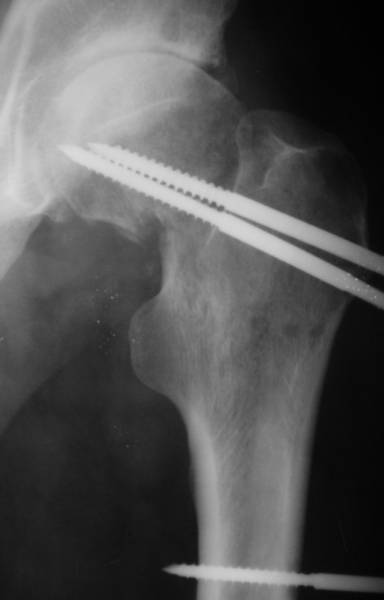

[Ortho] несросшаяся шейка бедра

Имя     : before.jpg

Url     : http://weborto.net:8080/pipermail/ortho/attachments/20070530/d5d32c11/attachment-0004.jpg